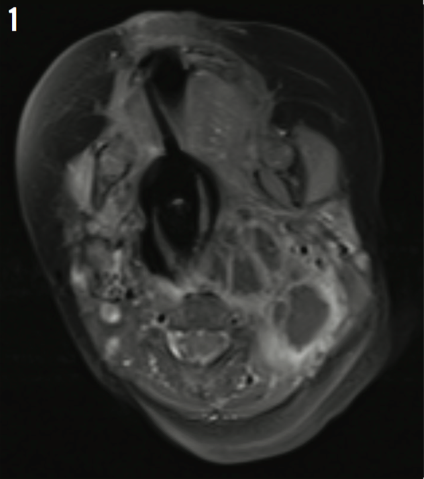

Dustin Paul, DO; Ebony Beaudoin, MD; Yaxi Zeng, MD; Kristin Ernest, MD; Mark Jason Sanders, MD; Lynnette J. Mazur, MD, MPH

The prevalence of polydactyly of the toes is 1.7 per 1000 live births compared with polydactyly of the fingers, the prevalence of which is 0.3 per 1000 live births.